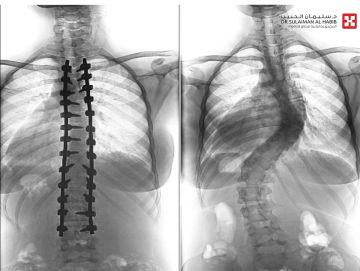

أجرى مستشفى الدكتور سليمان الحبيب بالفيحاء في جدة، بنجاح عملية جراحية معقدة، لتقويم انحراف مزدوج ومتزايد بالعمود الفقري 'جنف'، بدرجة '63' و'45'، وتثبيت ودمج الفقرات، لفتاة عمرها '17' عاماً، وأنهت العملية التي استمرت '6' ساعات، معاناة المراجعة مع عدة أعراض حادة استمرت معها لفترة طويلة، ذكر ذلك د. صلاح الدين خليفة استشاري جراحة العظام والعمود الفقري.

وجاءت المراجعة إلى المستشفى وهي تشتكي من تحدب وإنحاء جانبي، قيد حركتها وغير نمط حياتها، وعقب وصولها تم إخضاعها للفحوصات المخبرية وأشعة الرنين المغناطيسي Mri والأشعة السينية X- ray لكامل منطقة الظهر، حيث أكدت النتائج وجود انحراف مزدوج بزاوية '63'، و'45' درجة، وأخضعها الفريق الطبي لعملية جراحية، تم فيها تقويم العمود الفقري باستخدام البراغي والقضبان المعدنية، وتثبيت ودمج الفقرات، واستخدمت في العملية، مجموعة من أحدث الأجهزة الطبية منها الجراحة الملاحية Spinal NavigationSurgery، الميكروسكوب Pantero ومراقبة الأعصاب electrophysiology وساهمت هذه الأجهزة في نجاح التدخل الطبي.

وحولت المراجعة بمؤشرات حيوية مستقرة إلى العناية المركزة ووضعت تحت المراقبة لليلة واحدة، ومن ثم نقلت إلى غرفة التنويم وتحسنت حالتها، حيث تمكنت من المشي بعد '24' ساعة من العملية تحت إشراف اختصاصي العلاج الطبيعي، ومن ثم غادرت إلى منزلها بحالة صحية ونفسية ممتازة بعد '7' أيام، وأكدت فحوصات ما بعد العملية تعديل الميلان مع الحفاظ على سلامة الأعصاب، إضافة إلى أن المراجعة استعادت القدرة على الحركة والمشي بتوازن، والاستلقاء والنوم على ظهرها، فضلاً عن القوام والمظهر الطبيعي، بعد تعديل وضعية الحوض والكتف، كما أن طولها مع النجاح الكبير للتعديل زاد '5' سم. يذكر أن قسم جراحة العمود الفقري بالمستشفى تتوفر فيه أحدث التجهيزات ويقدم رعاية عالية الجودة على يد كفاءات طبية متمرسة، وتمكن خلال فترة الماضية من إنهاء معاناة عدد كبير من حالات انحراف العمود الفقري المعقدة بنجاح.